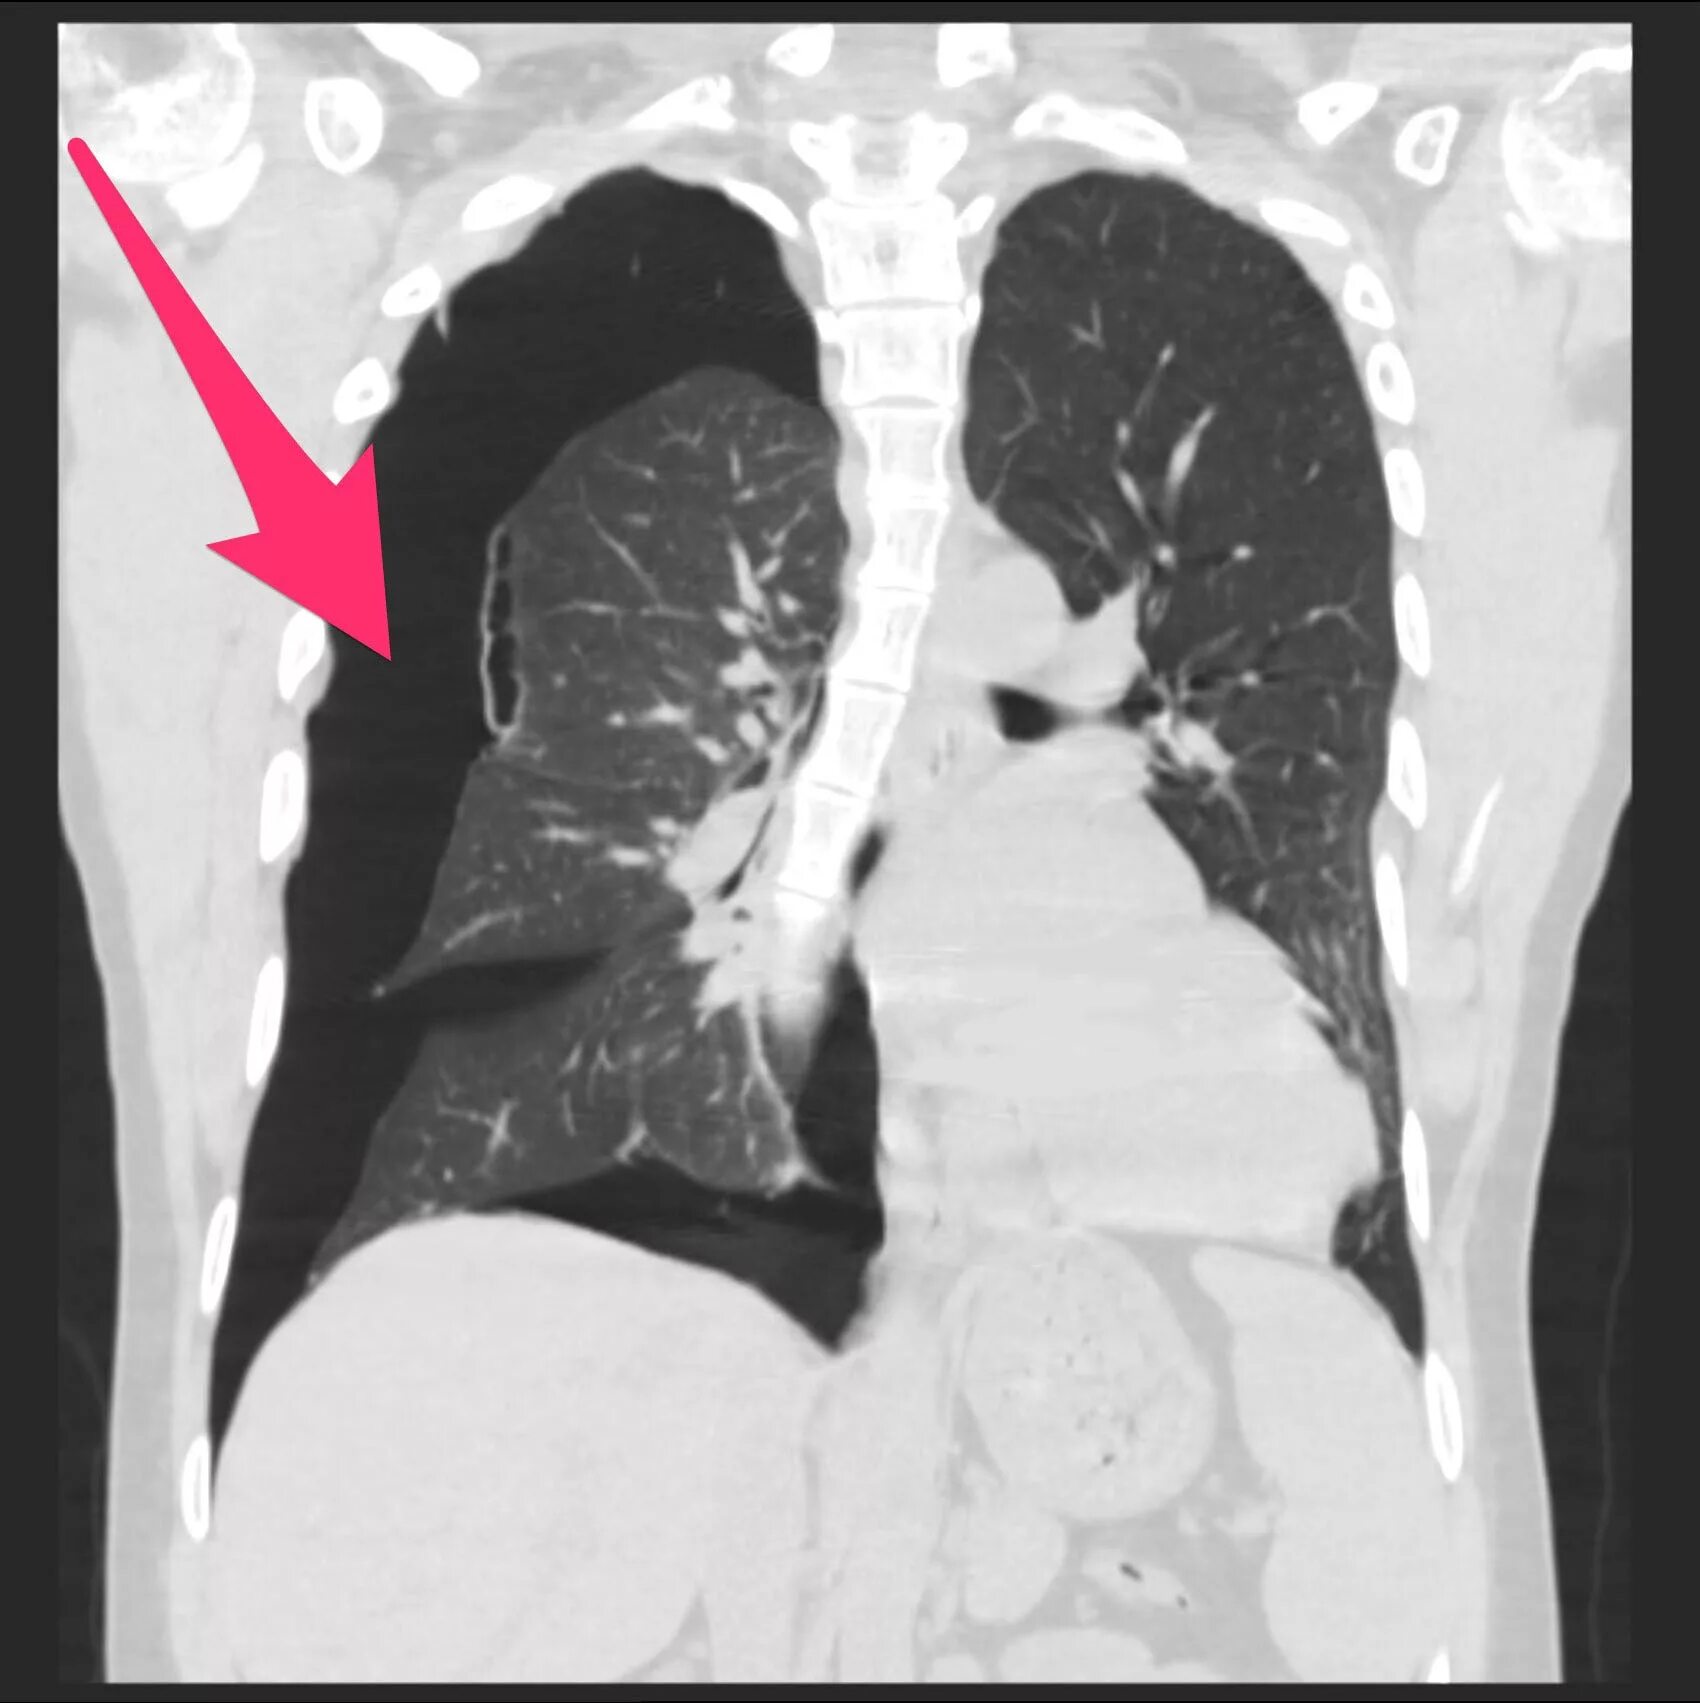

Флюорография видно что куришь электронную сигарету